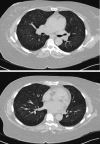

Hydralazine is a vasodilator used for the management of hypertension, heart failure, and hypertensive emergencies in pregnancy. It has been implicated in the causation of drug-induced lupus erythematosus (DLE) and rarely with ANCA-associated vasculitis (AAV), which may present as a pulmonary-renal syndrome and be rapidly fatal. Herein, we describe a case of hydralazine-associated AAV presenting as acute kidney injury with the use of early bronchoalveolar lavage (BAL) with serial aliquots to aid with diagnosis. Our case highlights how, in the correct clinical setting, BAL can act as a rapid diagnostic test to help guide quicker treatment to allow for better patient outcomes.